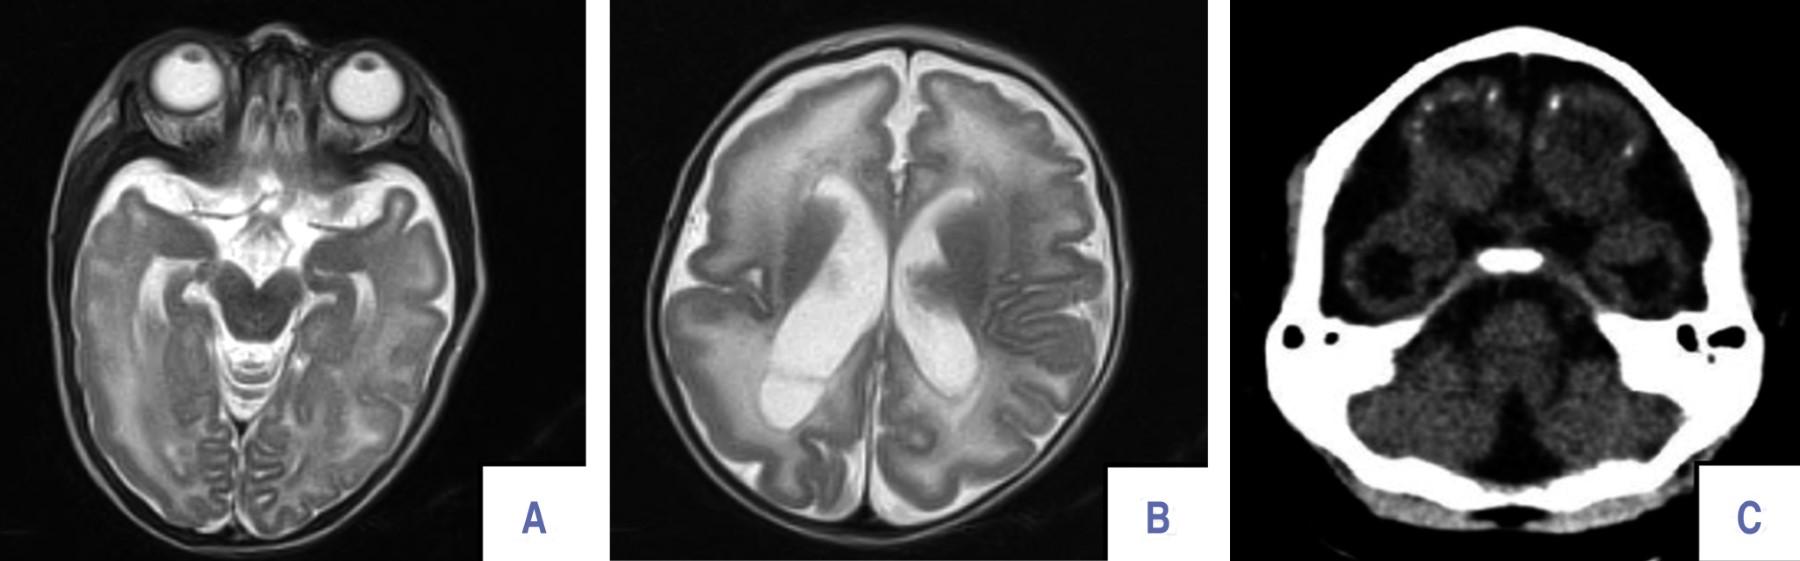

Neurodevelopmental follow-up of children with prenatal exposure to Zika virus

Introduction: Zika virus (ZIKV) is a flavivirus in pregnant women that can cause neurological conditions in their children. The aim of this study was to describe the neurodevelopment of 104 children with prenatal exposure to ZIKV, during the first 18 months of life. Material and methods: the patients were evaluated by neurological examination and the application of the Bayley III scale. Infection in mothers was confirmed with ZIKV NS1 IgG. Results: thirty-nine patients with neurodevelopmental delay (37.5%) and 17 patients with microcephaly (16.3%) were identified. Ocular abnormalities were detected in 25 (24%) patients, including involvement of the optic nerve, the retina, as well as the extraocular muscles. Conclusion: children of mothers with ZIKV infection during pregnancy have a high frequency of neurodevelopmental abnormalities.

Figure 1